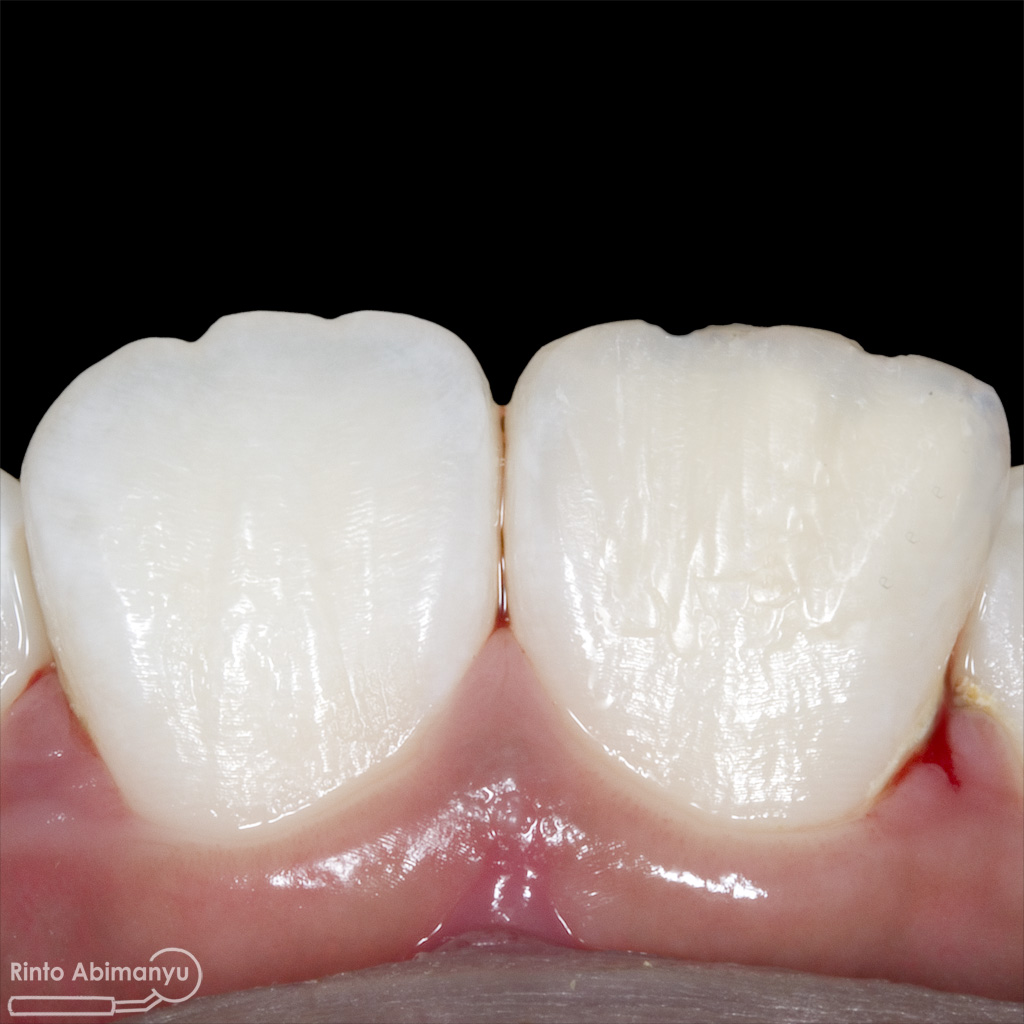

Kasus hari ini ceritanya datang seorang pasien wanita usia sekitar 50 an mengeluhkan gigi2 atas kirinya sering terselip makanan dan terkadang terasa senut-senut…

Pada pemeriksaan intra oral terlihat gigi 23 dan 24 mengalami karies dan cukup banyak sisa makanan terjebak disana…

Setalah pengisian usahakan kamar pulpa dibersihkan dari sisa2 siler dan kotoran2 agar bahan adhesive yang kita pakai untuk restorasi dapat melekat maksimal.. Untuk basis saya menggunakan X-tra Base (Voco) kemudian diatasnya memakai komposit Z 350 XT (3M)…